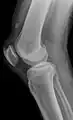

X-ray of a tear of the patellar tendon. On the left: The kneecap is pulled up. On the right: Significant dent in the soft tissue above the kneecap.